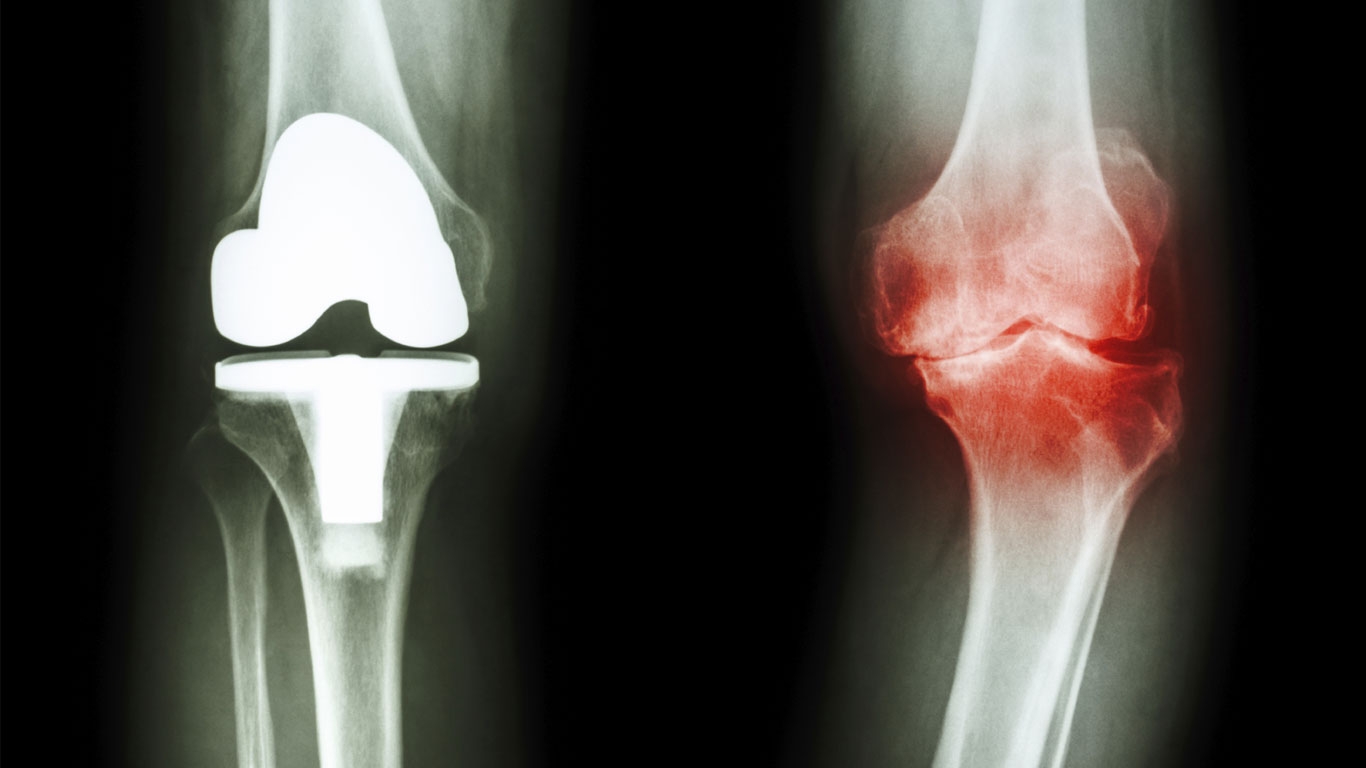

Verschleiß des natürlichen Polsters

Die Gelenke des menschlichen Körpers ermöglichen die Bewegung zwischen den Knochen. Damit sich diese möglichst reibungsarm gestaltet, sind die Gelenke an ihren Enden mit einer glasigen, elastischen Masse überzogen: dem Knorpel. Zusammen mit der Gelenkflüssigkeit federt er wie ein Stoßdämpfer die einwirkenden Kräfte ab. Ist dieses natürliche Polster beschädigt, reiben die Knochen direkt aufeinander – Bewegungen sind dann nur noch eingeschränkt und unter Schmerzen möglich.

Was bedeutet Arthrose?

Die Krankheit Arthrose leitet sich aus dem Griechischen her: In dem Begriff steckt das Wort „arthros“, was übersetzt „Gelenk“ bedeutet. Die Endung „-ose“ weist darauf hin, dass es sich um eine nicht entzündliche Erkrankung handelt. Das bedeutet, dass der Gelenkknorpel über einen längeren Zeitpunkt hinweg beansprucht wird und dadurch abnutzt oder verschleißt. Fälschlicherweise oft verwechselt, steht demgegenüber die Arthritis: eine Entzündung der Gelenke. Manchmal ist Arthrose begleitet von Schwellungen und schmerzhaften Entzündungen im Gelenk– in diesem Fall entsteht aus der Arthrose eine Arthritis.